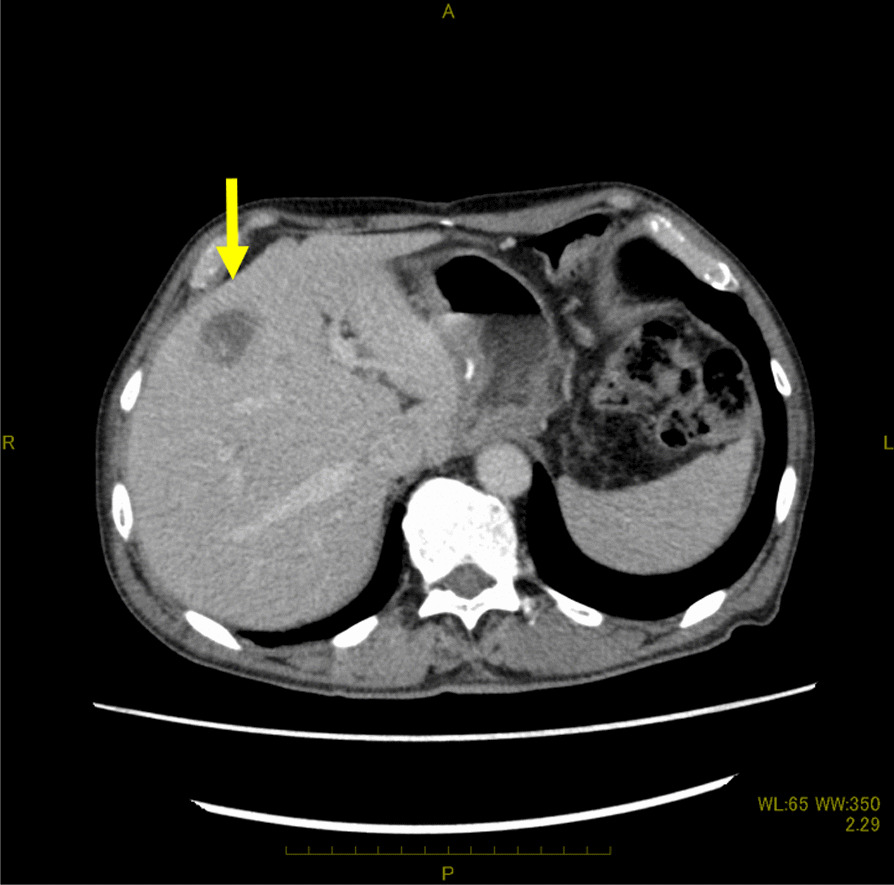

Five months after surgery, a computed tomography (CT) scan revealed a solitary liver metastasis measuring 21 × 15 mm in size in the S4 area (Fig. 1). The surgeons did not judge that the preoperative chemotherapy with CDDP in addition to 5-FU had failed. The patient underwent three courses of chemotherapy with CDDP in addition to 5-FU. During the three courses of chemotherapy, the patient suffered from side effects of chemotherapy including nausea and loss of appetite. Follow-up positron emission tomography PET after the three courses of chemotherapy reveled two new lymph node metastases in the paraaortic area (Fig. 2). The surgeons judged that the first-line chemotherapy had failed because the lymph node metastases showed an increase in size.

Fig. 1.

Axial enhanced computed tomography scan images of the abdomen showing a low-enhanced lesion of 21 × 15 mm in size in the S4 area (yellow arrow)